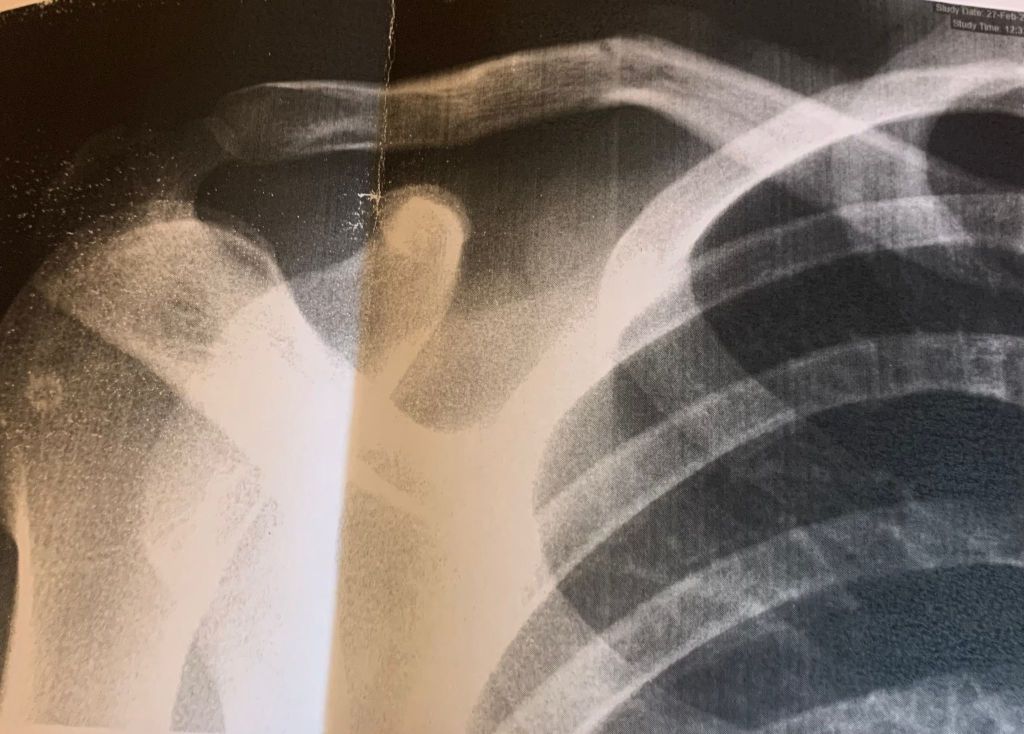

El ciclista británico Louis Sutton, del Brocar Alé, viaja el miércoles a Inglaterra donde se recuperará de una fisura de clavícula que sufrió el pasado domingo en Don Benito durante la celebración del Circuito del Guadiana, primera prueba de la Copa de España élite y sub 23. En principio no debe pasar por el quirófano y tiene por delante al menos tres semanas para recuperarse antes de volver a ponerse el dorsal. “Hice el afilador con otro ciclista y no tuve tiempo de reaccionar y frenar antes de chocar. Íbamos a unos 60 kilómetros por hora”.